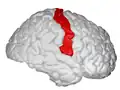

Primary cortices, including primary somatosensory cortex (labeled in purple) Postcentral gyrus, showed on the right hemisphere.

Postcentral gyrus, showed on the right hemisphere. Postcentral gyrus highlighted in green on coronal T1 MRI images